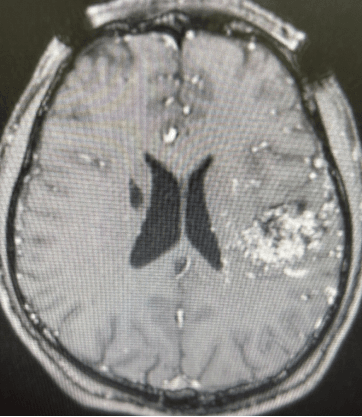

脑转移瘤克星—HyperArc“超弧刀”一键式清除

病例分享这是一名中年女性,乳腺癌术后4年余。因出现头痛、头晕,伴肢体活动障碍半个月来我院就诊,检查显示患者脑部有7处转移瘤,其中2处